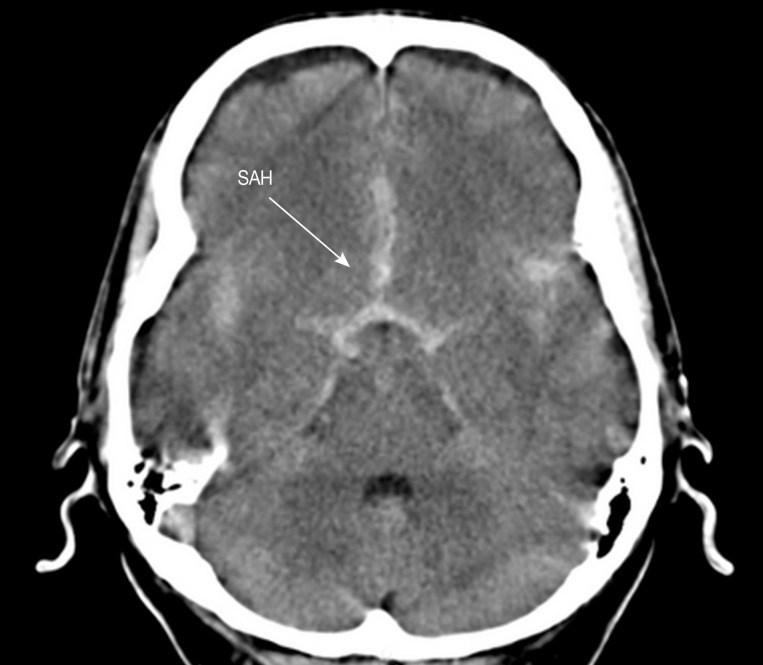

The inclusion criteria included non-traumatic SAH patients for whom 1) results of CT brain imaging (

Fig. 1) or MR imaging of the brain were available, 2) results of CT angiography (CTA) or MR angiography (MRA) or 3-dimensional digital subtraction cerebral angiography (DSA) were available (

Fig. 1Non-contrast CT axial view showing hyperdense area of subarachnoid hemorrhage (SAH) along the interhemispheric fissure.